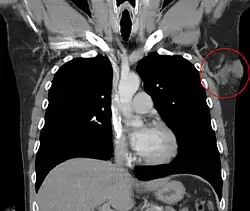

.jpg)

O tratamento depende do tipo de câncer, a localização do câncer, idade do paciente, e se o câncer é primário ou um retorno. Deve-se olhar para o tipo específico de câncer de pele (carcinoma basocelular, carcinoma espinocelular ou melanoma) de interesse, a fim de determinar o tratamento adequado exigido. Por exemplo, no caso de um homem idoso frágil, com problemas médicos múltiplos complicador, com carcinoma basocelular de difícil acesso do nariz podem justificar a terapia de radiação (taxa de cura ligeiramente inferior) ou mesmo não intervir na área. Quimioterapia tópica pode ser indicado para o carcinoma de grandes células basais superficiais para um bom resultado estético, ao passo que podem ser inadequados para o carcinoma invasivo nodular basais ou carcinoma de células escamosas invasivo. Em geral, o melanoma é pouco sensível à radiação ou quimioterapia.